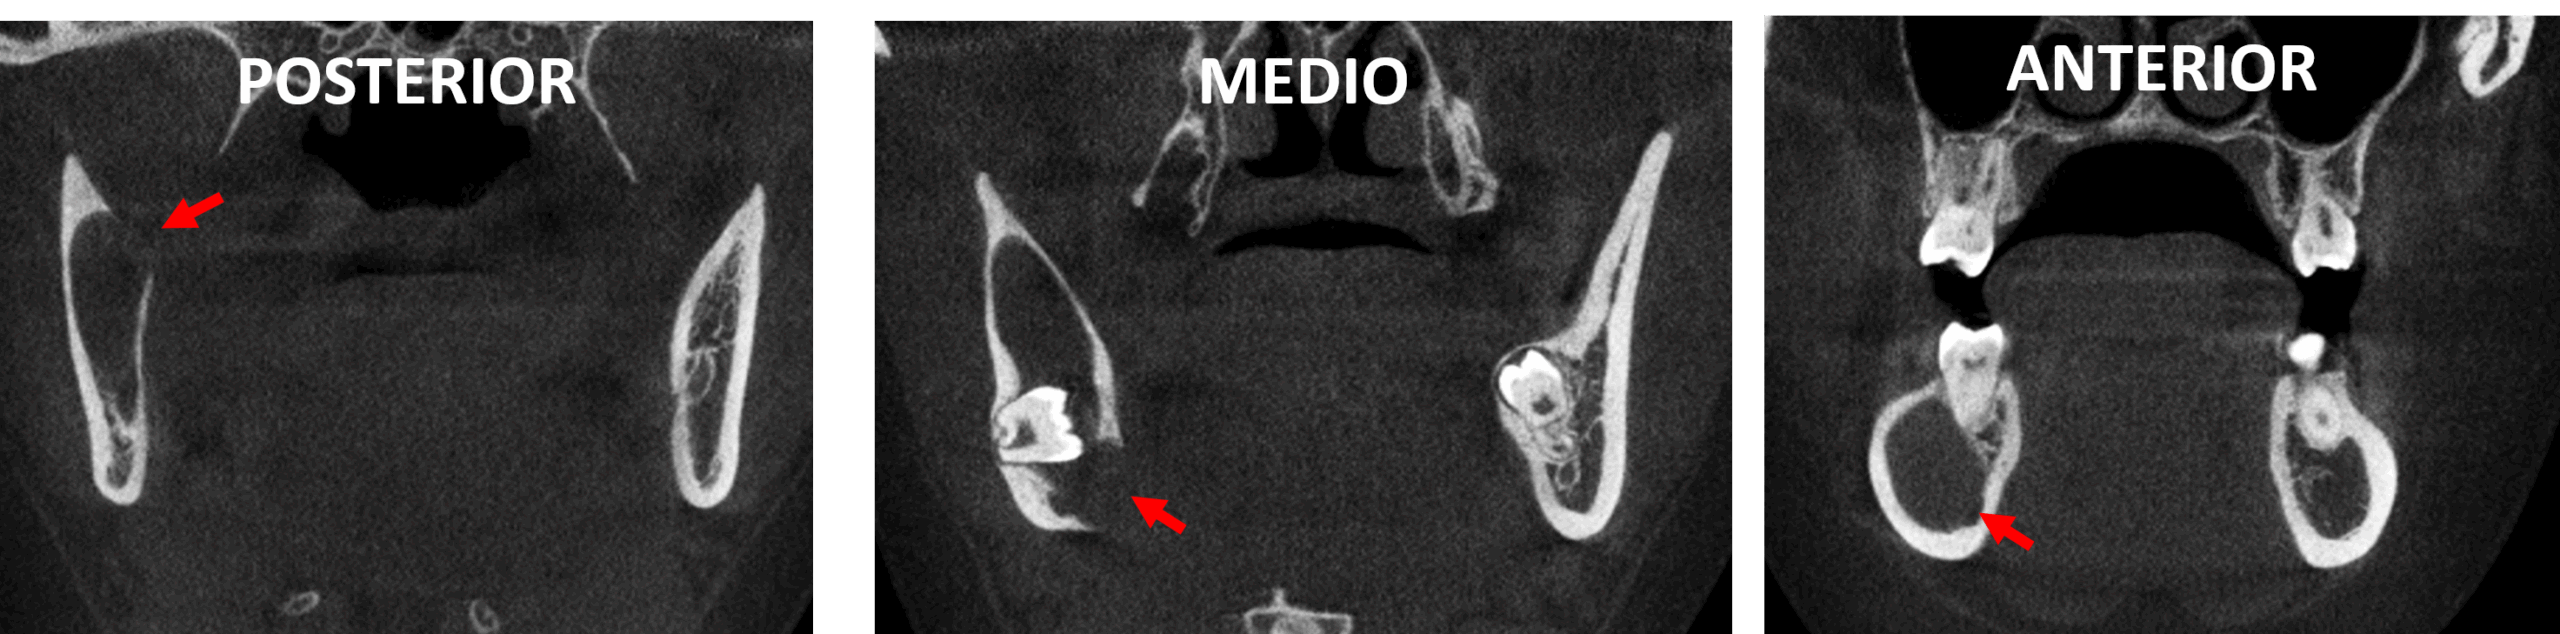

En cortes coronales (Fig.4) se observa el marcado adelgazamiento y aparente erosión de la cortical interna de la rama ascendente en el corte posterior y medio (flechas rojas). Se consideran signos radiológicos de un probable queratoquiste odontogénico.